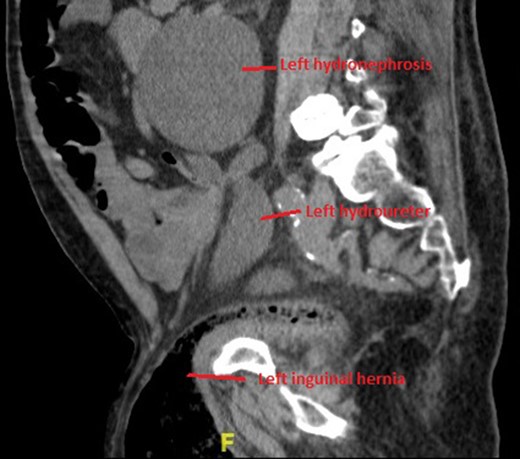

Non-contrast CT of the chest, abdomen and pelvis was performed on admission looking for malignancy considering his visible haematuria and significant unintentional weight loss. This demonstrated severe bilateral hydronephrosis and hydroureter, which was more prominent on the left side (Figs 2–4). The left ureter tapered in the pelvis and neither the bladder nor either ureter was seen in the inguinal canal and a large, left-sided inguinoscrotal hernia was seen containing distal colon. Bilateral loss of renal cortical thickness, a potassium of 6.0 mmol/L and an eGFR of 9 mL/min was suggestive of chronically obstructed kidneys.

Coronal section of CT demonstrating severe left-sided hydronephrosis and left ureter compressed distally by hernia. Left distal ureter is closely related to neck of hernia sac at the deep ring.